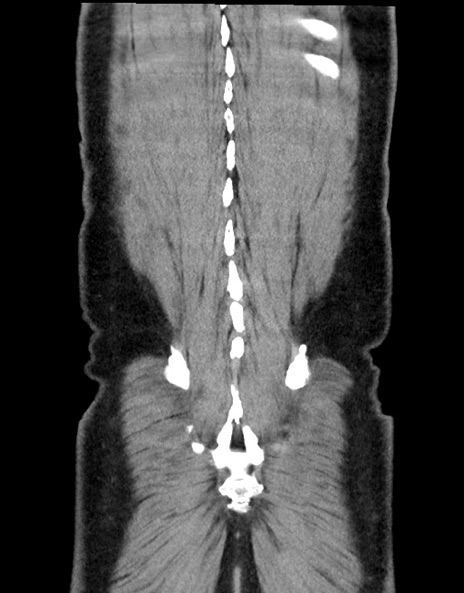

症例15(冠状断像)

【症例】70歳代男性

【主訴】腹痛

【現病歴】今朝から腹痛あり。全体的に痛い。特に左上の方。排ガスが今日はない。冷や汗が出る。

【既往歴】直腸癌術後

【身体所見】左側腹部〜上腹部に圧痛あり。腹膜刺激症状明らかなではない。軽度反跳痛。左下腹部に術後瘢痕あり。

【データ】WBC 7700、CRP 0.02